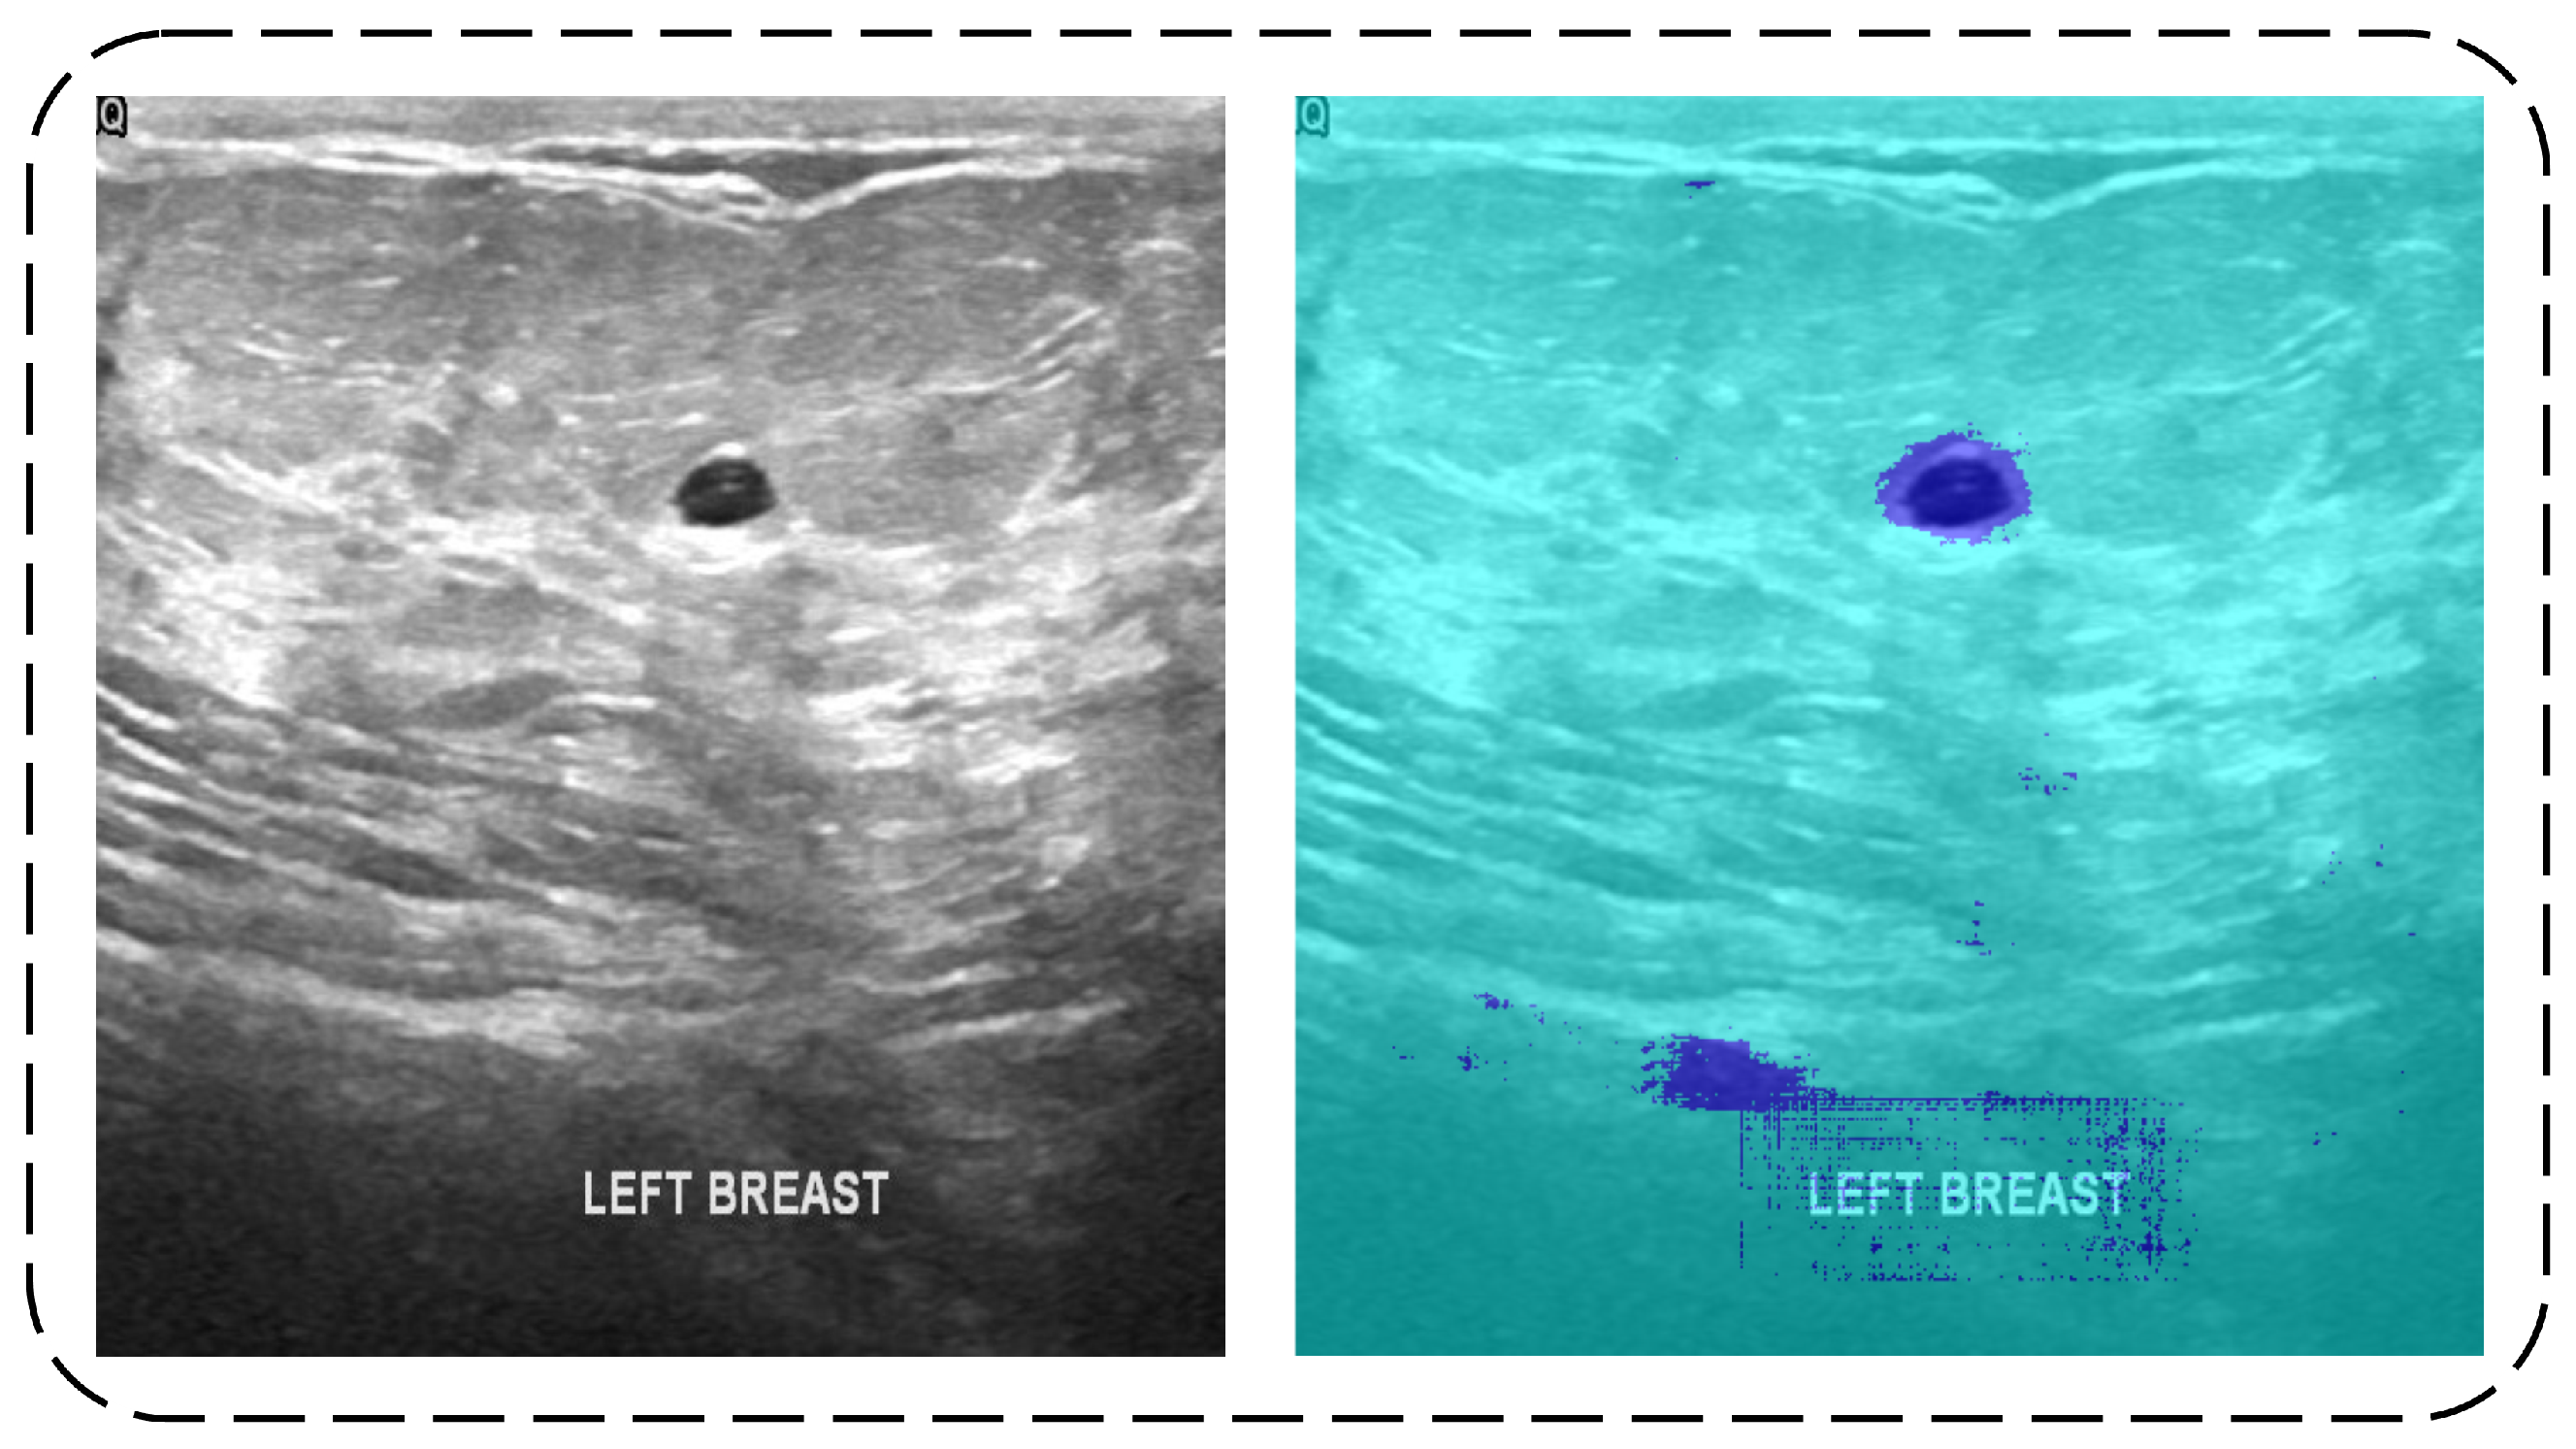

3.1. Segmentation

3.1.1. Dilated Semantic Convolutional Neural Network

3.1.2. Erosion